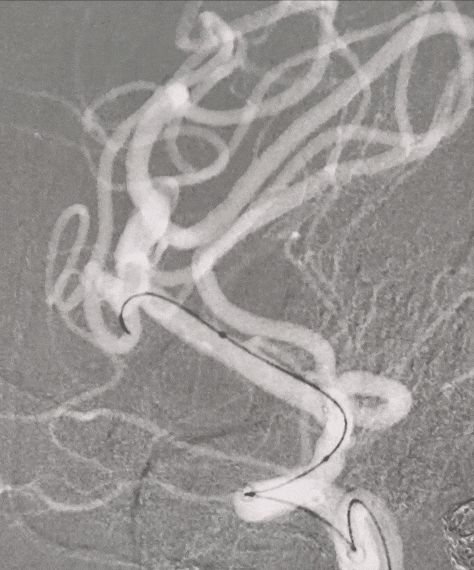

术前造影

CTA提示:右侧大脑中动脉动脉瘤。

造影提示:动脉瘤瘤颈累及上下干支,下干支与M1成角较锐S弯;患者右侧颈内动脉非常迂曲。

3D造影成像:动脉瘤大小约3.7*3.1mm。

其它颅内血管未见异常。